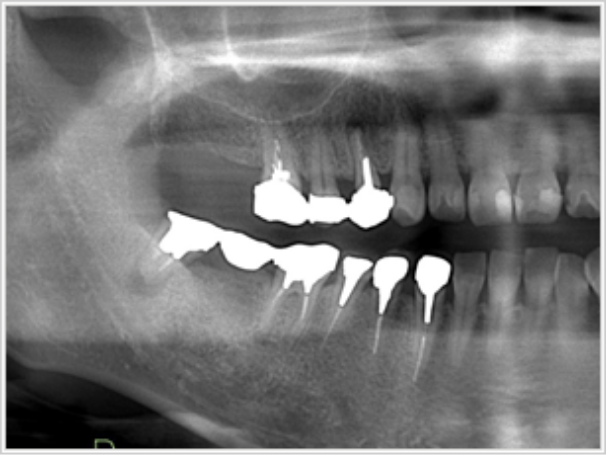

右上下奥歯1本欠損

- 治療内容

- 下はブリッジをしていた親知らずが駄目になり、当日親知らずを抜いて右下7番に1本。

上は10年ほど無く、一緒に治療をいたしました。インプラントはストローマン。

- 治療期間

- 2ヶ月間(インプラント入れてから完成まで)

奥歯(銀歯2本)

60万円(税込)